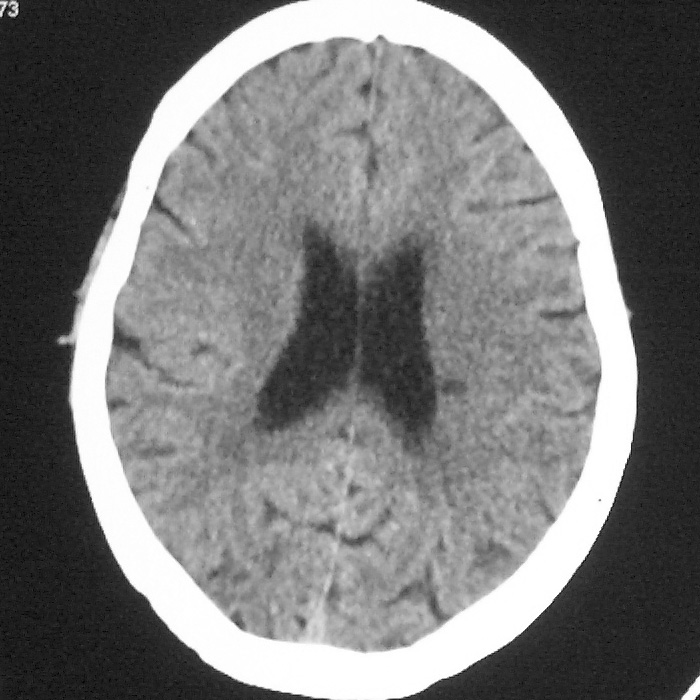

f,70y,口角歪斜、流涎、吐词不清三天

左侧大脑基底节区点状低密度影,边缘清楚,左侧腔梗或软化灶,没什么问题啊?

症状这么明显的话一般不会是单纯面神经麻痹引起的,最好做个mri,如果确实没有问题的话才能考虑面神经麻痹,毕竟这两种病的治疗和预后不一样,这个病人还有脑白质疏松。

左侧半卵圆中心腔梗应当比较明确,右侧基底节好象不明显,不好说,做个mri明确吧

双侧多发腔梗

右侧基底,左侧半卵圆中心腔梗

1、右侧基底,左侧半卵圆中心腔梗。2脑萎缩。

左侧腔隙性梗塞灶,脑萎缩。

左侧基底节区示点状低密度灶,边界清楚,密度均匀,余所示无著变。

意见:腔隙性脑梗塞(左基底节区)

各位老师,报告这么写可以吗?右侧我没有看出来。

左侧半卵圆中心,右侧基底节腔梗。再加个脑萎缩吧

双侧多发腔梗 脑萎缩